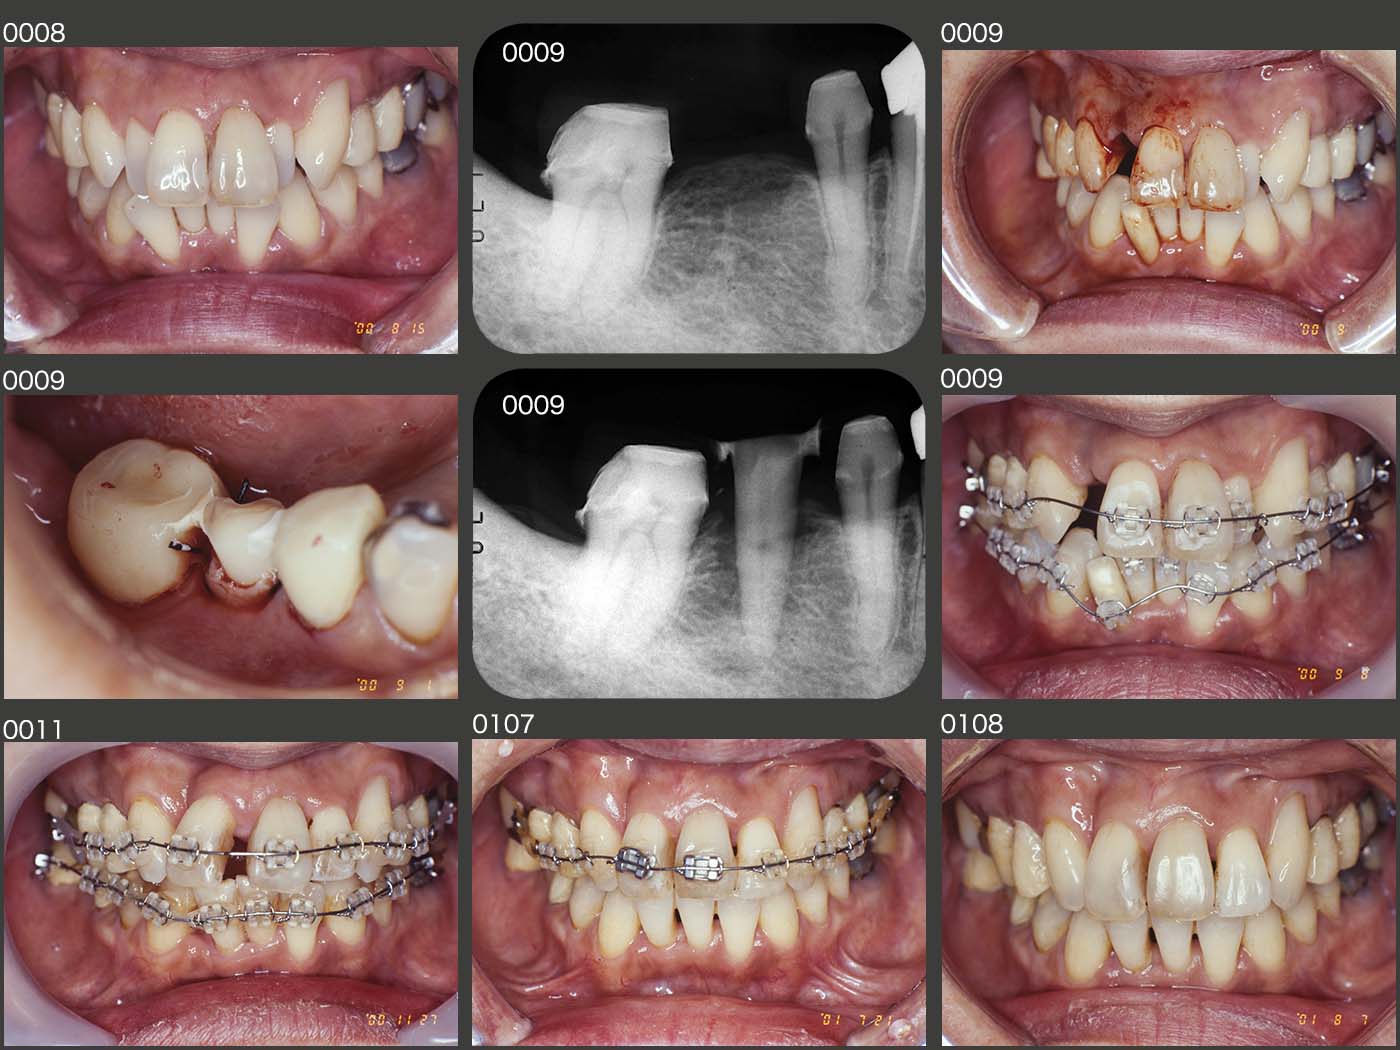

2000年2月初診,54歳女性.主訴は,色々治したい.主訴の一つである上下顎前歯の審美性の改善について,セット・アップ模型を用い治療後の形態を提示した.前歯部を内側に入れるためのスペース確保のために,抜去する歯を上下それぞれ最小限の1本にしたい.また,臼歯部の咬合は変化させないという治療方針をたてた.しかし,歯列の正中がずれる欠点があることを説明したところ,患者さんはこの方針での治療を希望された.なお歯周ポケットは,右下7の遠心が7mm以外,特に問題はなかった.

前歯の歯科矯正を行うにあたって,左側の上下6にレジン前装のメタル暫間被覆冠を装着し,固定源の強度を確保した.また小臼歯部に装着されている冠を除去し,連結固定しやすく,またブラケットが外れにくいレジン暫間被覆冠を装着した.

2000年9月,スペース確保のために右上2を抜去したが,廃棄するのはもったいないので,右下⑦6⑤ブリッジを除去し,ポンティック部に歯の移植を行った.右下2もスペース確保のために抜去の予定であるが,右下1,3の下部鼓形空隙を大きくしないために,矯正的挻出を行い,歯槽骨の増大を図ったうえで抜去した.

動的矯正期間は00年9月から01年7月までの11ヵ月である.